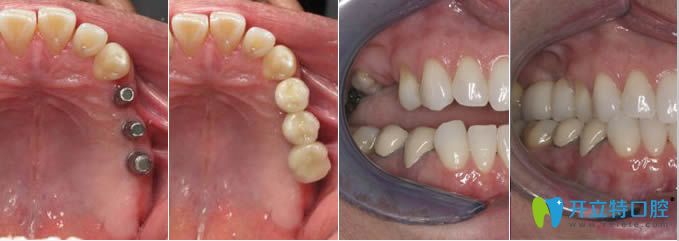

2、多顆牙缺失、單顆牙缺失種植前后對比圖:

弘和口腔多顆牙缺失及單顆牙缺失種植前后對比圖

【弘和五大種植系統(tǒng)】:

韓國奧齒泰種植體、德國費(fèi)亞丹種植體、瑞典Nobel種植體、美國百康種植體、美國3I種植體。